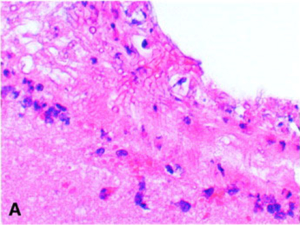

This is a series of HE and PAS stained slides demonstrating intra-sinus inflammation and fungal structures with Aspergillus fumigatus in the rabbit.

Images: Comparative Efficacies, Toxicities, and Tissue Concentrations of Amphotericin B Lipid Formulations in a Murine Pulmonary Aspergillosis Model